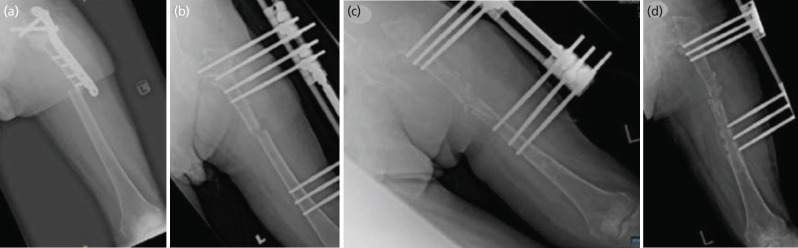

骨不连是指骨折修复过程中出现的断裂,可通过连续的临床和影像学评估来识别。脓毒性骨不连和无菌性骨不连的区别是必要的,因为治疗策略是根本不同的。骨不连最常用手术治疗,因为它有助于提供机械稳定性和良好的生物环境来促进骨愈合。然而,也有保守治疗的选择,即使用功能支架进行适当的固定,这是外科手术的另一种选择,在胫骨不连病例中被广泛报道。迄今为止,还没有功能性支架成功治疗股骨骨不连的病例报道。本病例报告详细介绍了使用功能性支架成功治疗一位因骨折相关感染导致股骨不愈合的智障男士。

Non-union refers to a disruption in the process of fracture repair, which can be identified through sequential clinical and radiographic assessments. The distinction between septic and aseptic non-union is essential because the treatment strategies are fundamentally different. Non-unions are most often treated surgically as it helps to provide both mechanical stability and good biological environment to promote bone healing. However, there is also the option of managing it conservatively by proper immobilisation using functional brace which is an alternative for surgical procedures and widely reported in tibia non-union cases. To date, there has been no reported case of femur non-union successfully treated with a functional brace. This case report details the success of treatment using a functional brace in a mentally disabled gentleman who sustained a femur non-union following a fracture related infection.